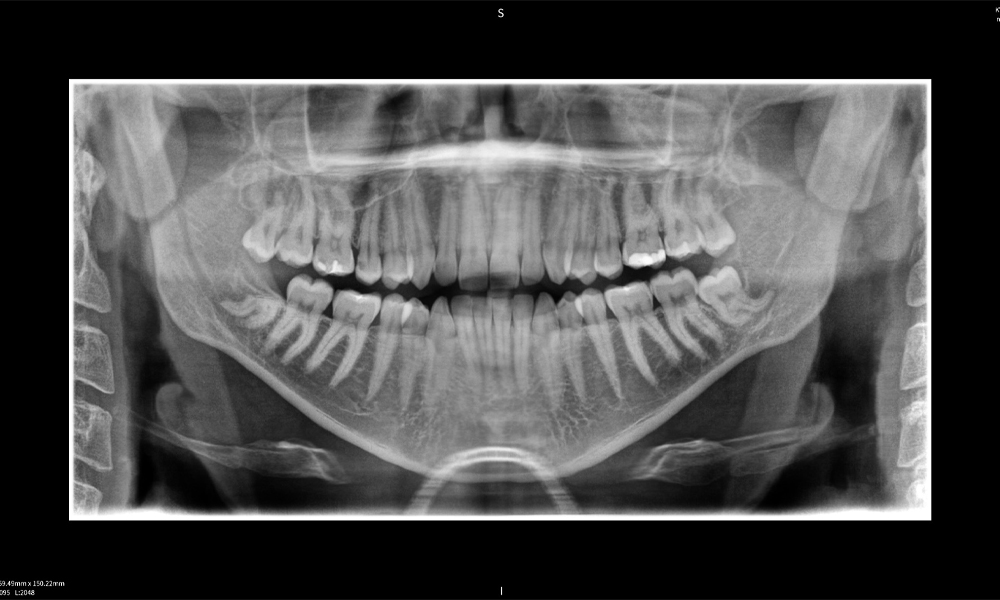

Abbildung e: Bildgebungsergebnisse von Seethrough Max vor einem schwarzen Hintergrund.

Abbildung e

Abbildung e: Panoramaröntgenaufnahme dient der initialen Beurteilung und zeigt die allgemeine Zahnstellung sowie mögliche pathologische Veränderungen auf. Insbesondere ist auf der rechten Seite (Zahn 48) die Situation nach einer Kronenamputation durch einen externen Behandler ersichtlich. Die beiden stark gekrümmten Wurzeln verbleiben in enger topographischer Beziehung zum Nervus alveolaris inferior im Knochen. Dies deutet auf eine bewusste Entscheidung zur Vermeidung eines erhöhten Risikos einer Nervenläsion während einer vollständigen Extraktion hin und stellt einen klinisch relevanten Befund dar. Zusammenfassend liefern die CBCT-Aufnahmen mit Seethrough Max entscheidende Informationen über die komplexe Anatomie und die kritische Beziehung zwischen den Weisheitszähnen und dem Nervus alveolaris inferior. Diese detaillierte präoperative Diagnostik ist unerlässlich für die sichere und erfolgreiche Durchführung chirurgischer Eingriffe im Unterkieferbereich.